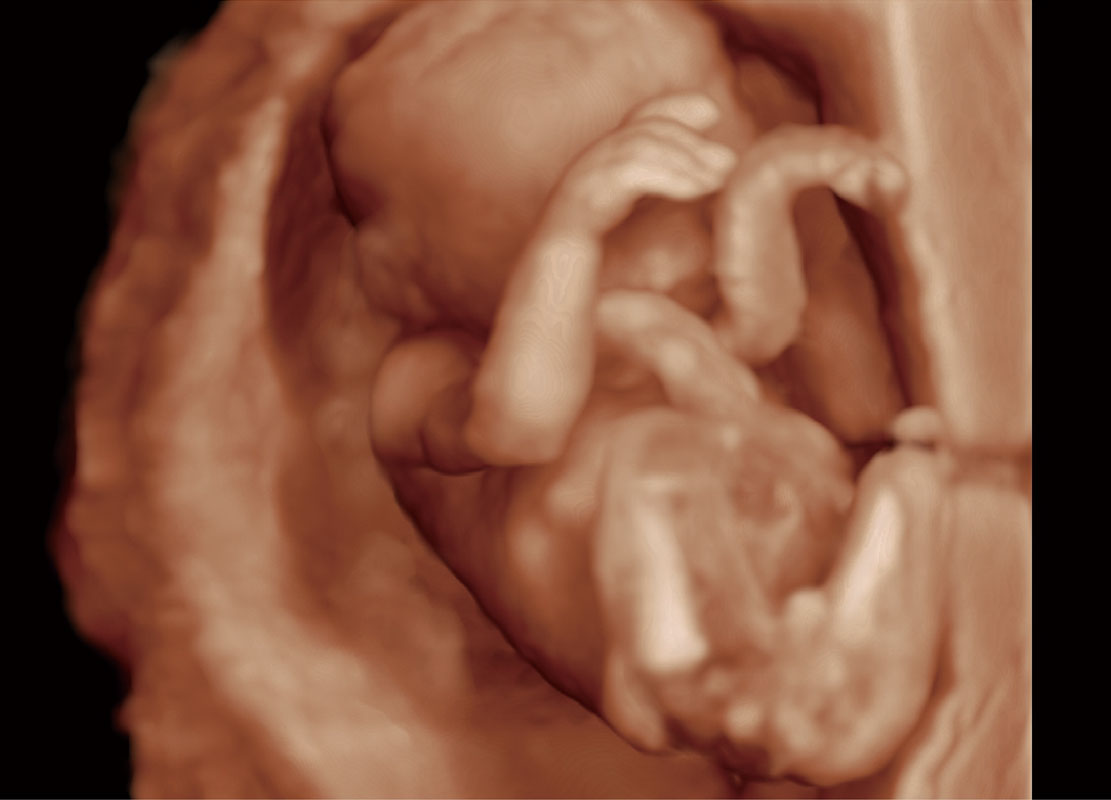

P60在胎儿早孕期超声筛查中为您带来优异的图像质量。

高分辨率容积成像-早孕胎儿

P60提供简单易学易用的高端诊断工具,为您中晚孕筛查提供快速清晰的解剖信息。